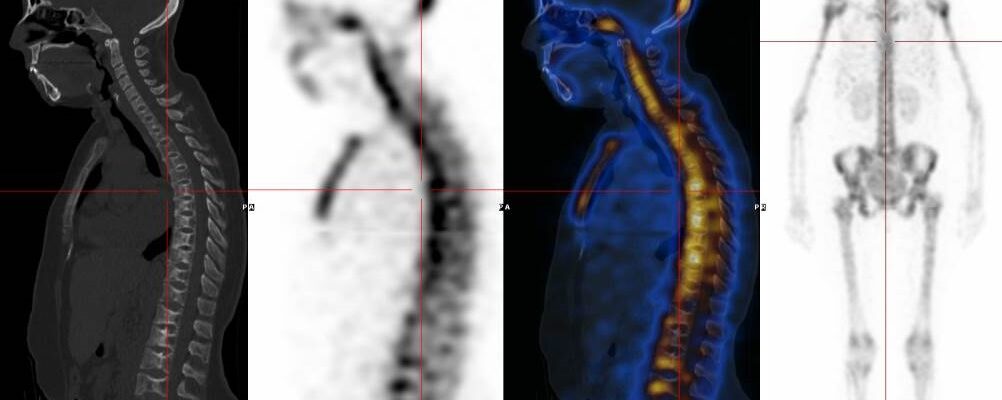

Patient suivi depuis 2013 pour carcinome lobulaire infiltrant.

Reprise évolutive ganglionnaire et secondaire en 2016. Reprise évolutive ganglionnaire rétropéritonéale en 05/2018. Évaluation cours de traitement.